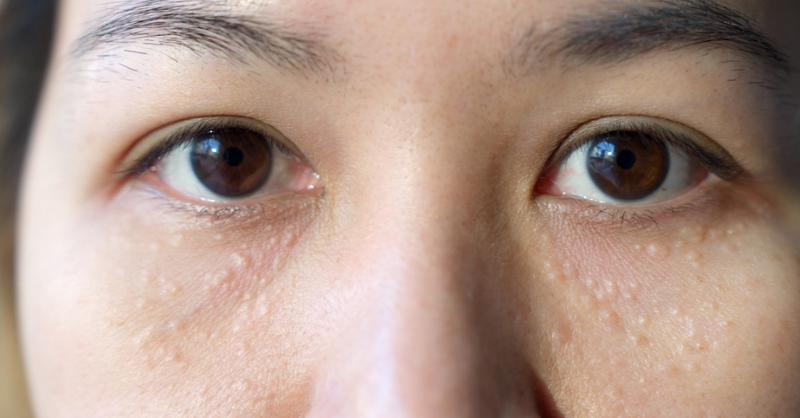

White Bumps on the Skin: What Do They Mean?

They show up quietly, like tiny white grains sitting on your skin. Often around the nose or the eyes, they appear without warning and stubbornly refuse to go...